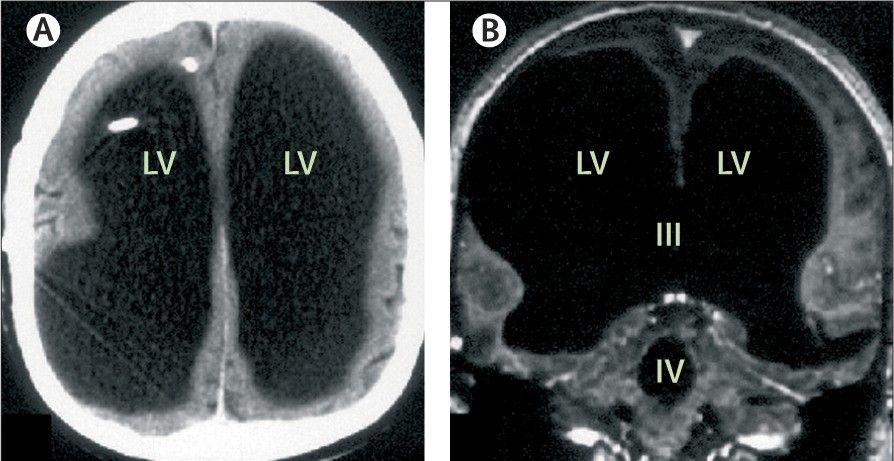

Schwäche in den Beinen ist ein häufiges Symptom, das durch eine Vielzahl von Faktoren verursacht werden kann. Im Zuge der neurologischen Abklärung brachten CT- und MRT-Scans des Kopfes die Ursache der Symptome ans Tageslicht: Dort, wo eigentlich das Gehirn sein sollte, war einfach nichts, wie die Ärzte in ihrem Bericht festhielten.

Hydrocephalus

Es stellte sich heraus, dass der Mann an einem schweren Fall von Hydrozephalus ("Wasserkopf") litt. Auf den Scans erscheint statt Hirngewebe nur schwarzer Raum, wo sich Flüssigkeit angesammelt hatte. Dies führte dazu, dass sein Gehirn gegen den Rand seines Schädels gedrückt wurde. Infolgedessen wurde auch festgestellt, dass sein Schädel vergrößert war.